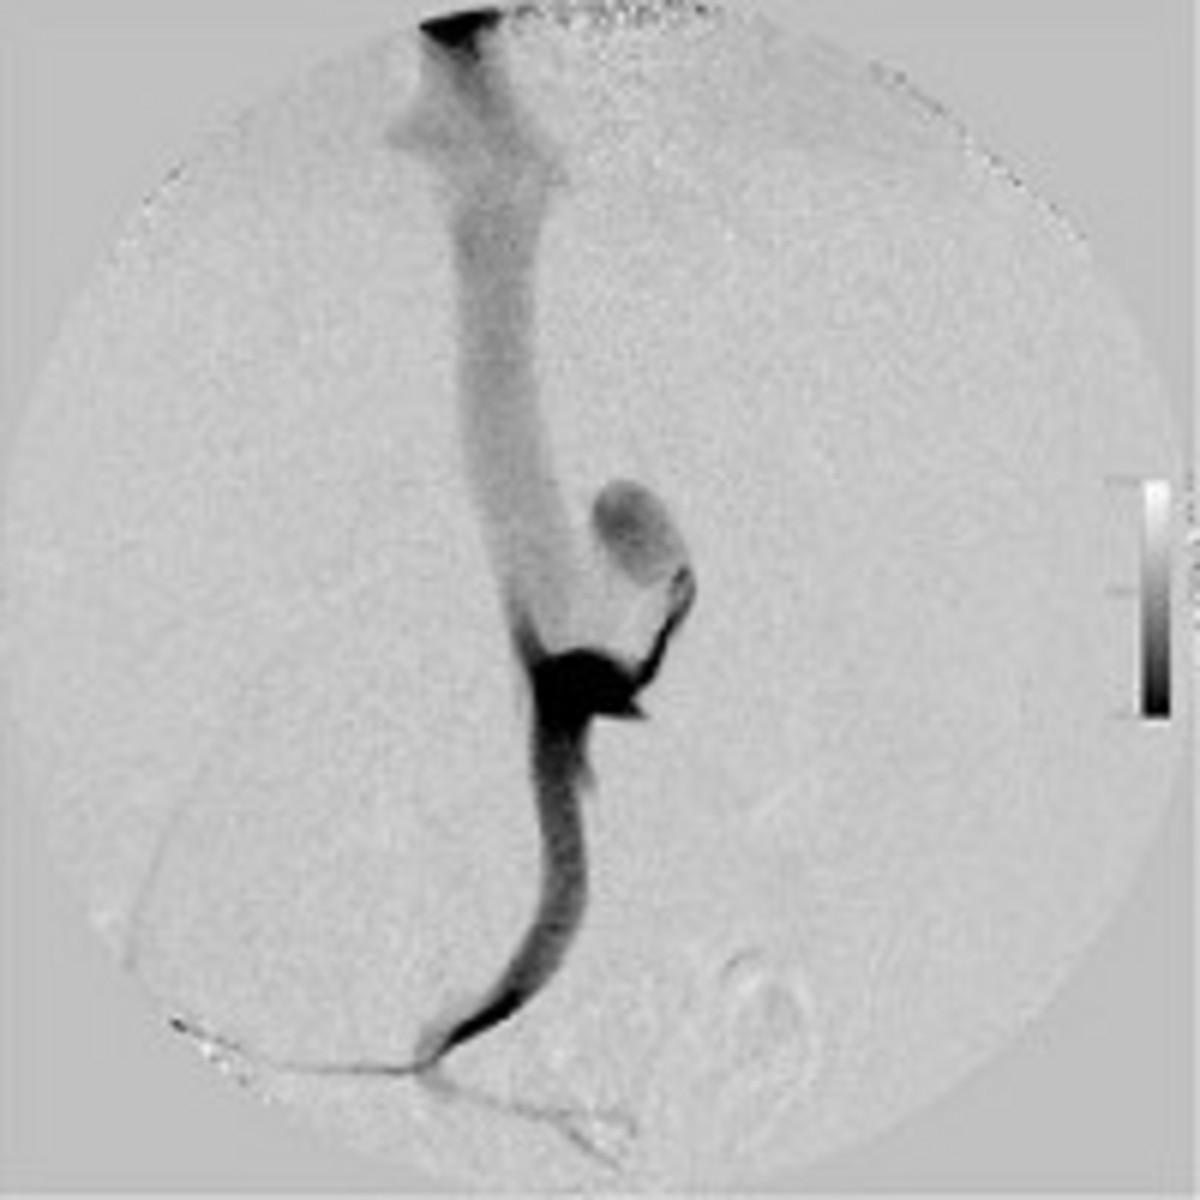

症例に全身麻酔を施した後、上腹部を正中切開し、腸間膜静脈にカニュレーション後、門脈圧の測定および門脈造影(図3)を行いました。シャント血管を同定し(図4)、仮結紮後に門脈圧測定および門脈造影(図5)を実施したところ、門脈圧の上昇が認められたため、門脈圧が過度に上昇しない程度に部分結紮にとどめ、手術を終了しました。手術時間は約60分でした。これらの手術中、約20分おきに血糖値をモニタリングしました(図6)。手術開始20分後で血糖値が158 mg/dlに上昇していましたので、グルコースの流量を0.1 g/kg/hrに減量しました。手術開始後40分では136 mg/kg/dlでしたので、この流量のまま手術終了まで維持しました。手術終了後も血糖値をモニターしながら、輸液中のグルコース濃度を調節して維持しました(図7)。

図3 門脈造影像(DSA)